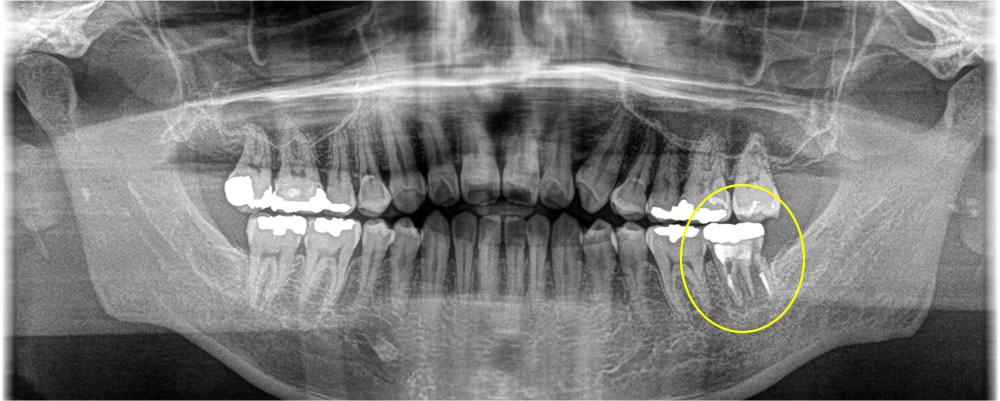

痛みのある歯を抜歯してインプラントで治療した症例

年齢

60代

性別

女性

症例を見る